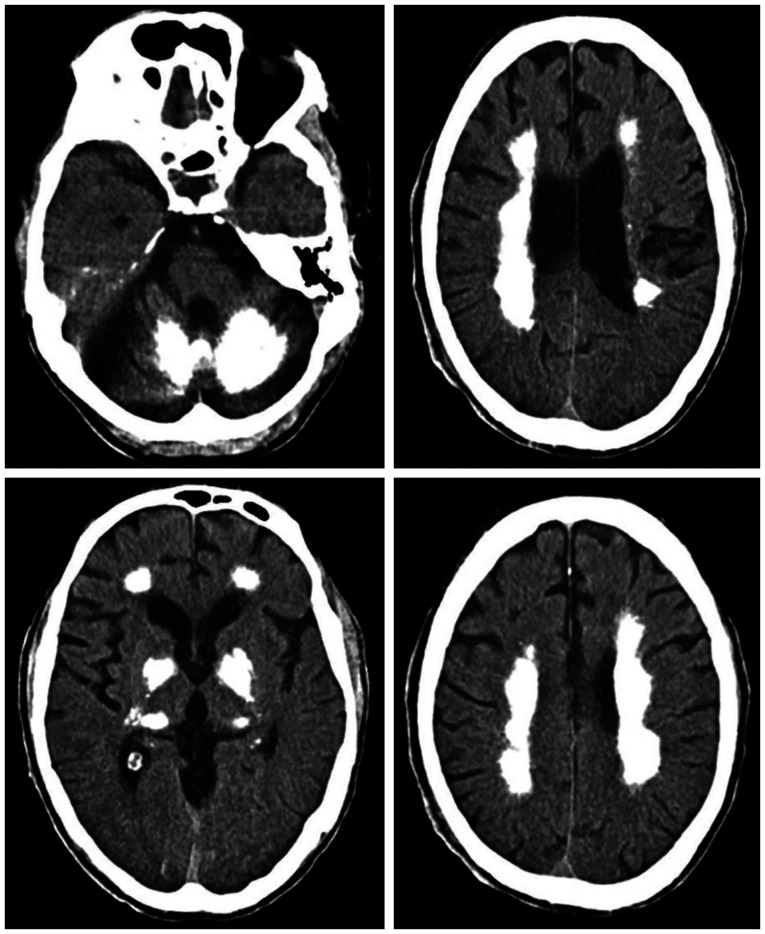

Novel MYORG Variant Linked to Primary Familial Brain Calcification.

与原发性家族性脑钙化有关的新型 MYORG 变异基因